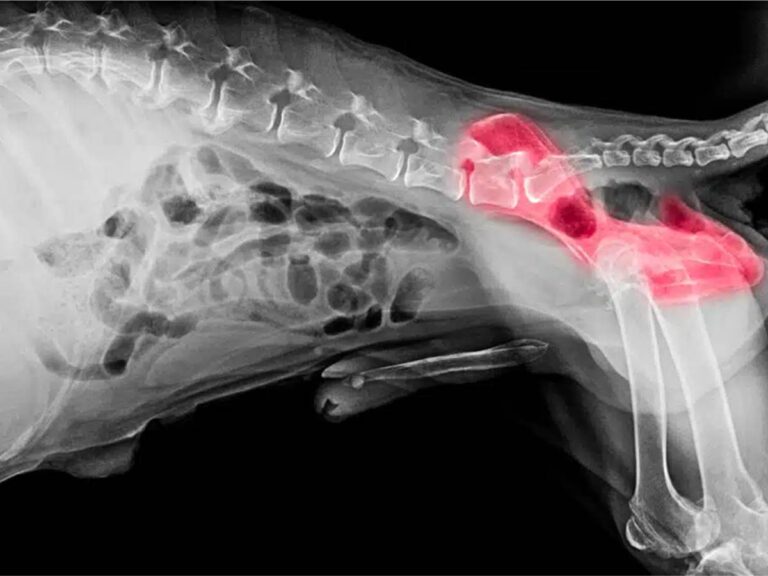

JPS is a minimally invasive surgical procedure designed to modify the growth of the pelvis in young puppies. By fusing part of the pubic symphysis (the cartilage connecting the two halves of the pelvis), this surgery encourages the hip socket to develop a tighter fit around the femoral head, reducing joint laxity and improving stability.

In dogs with hip dysplasia, the hip socket is too shallow, causing the femoral head to shift and grind against the joint improperly. Over time, this leads to arthritis, pain, and mobility issues. By altering pelvic development, JPS improves joint congruity and reduces stress on the hip joint, preventing these issues before they start.